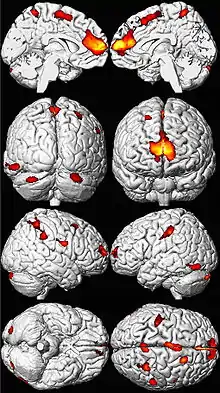

.png.webp)

Lead poisoning can cause a variety of symptoms and signs which vary depending on the individual and the duration of lead exposure.[23][24] Symptoms are nonspecific and may be subtle, and someone with elevated lead levels may have no symptoms.[25] Symptoms usually develop over weeks to months as lead builds up in the body during a chronic exposure, but acute symptoms from brief, intense exposures also occur.[26] Symptoms from exposure to organic lead, which is probably more toxic than inorganic lead due to its lipid solubility, occur rapidly.[27] Poisoning by organic lead compounds has symptoms predominantly in the central nervous system, such as insomnia, delirium, cognitive deficits, tremor, hallucinations, and convulsions.[22]